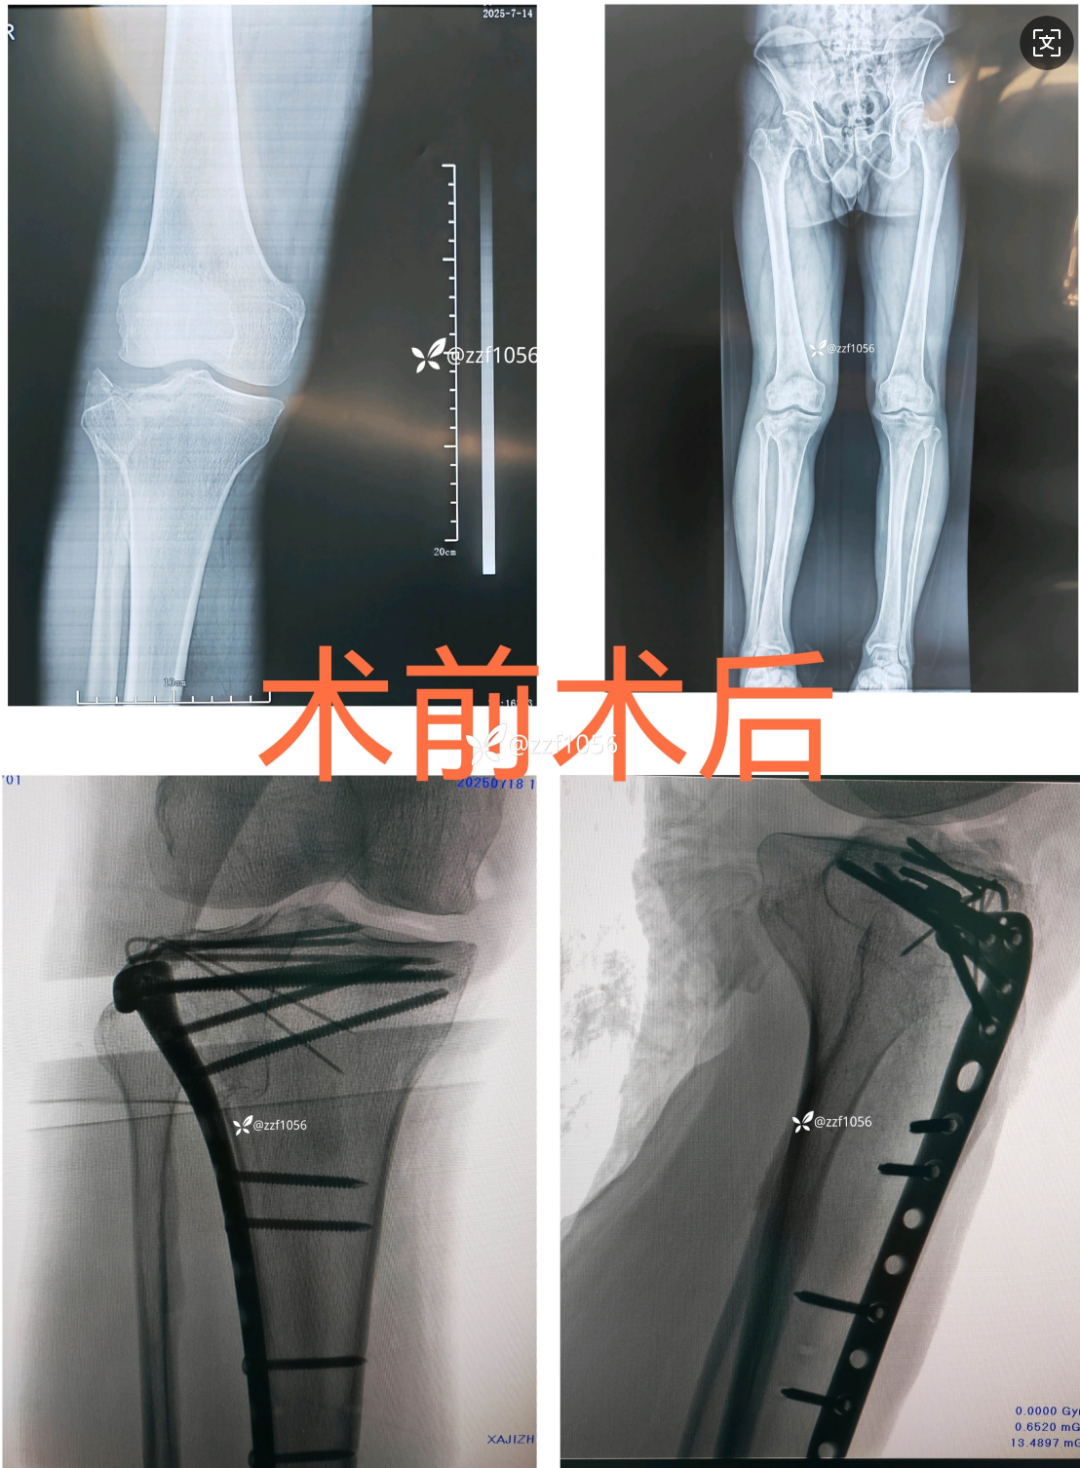

患者诊断为右侧胫骨平台骨折,I 类切口,行切开复位钢板内固定术。

手术前后 X 片:

术后第 6 天手术伤口出现红肿,第 10 天引流出明显脓液。

细菌培养结果提示生长科氏葡萄球菌,怀疑骨内感染或者关节内感染。